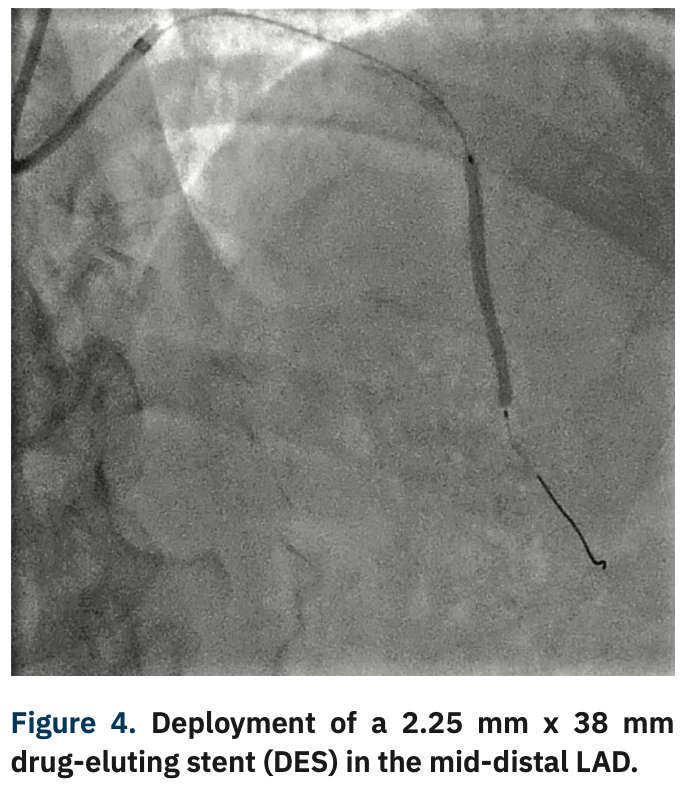

Like all centers, we are using more and more advanced imaging, but it is not uncommon for a lesion to be unpredictably difficult to dilate and more heavily calcified than is readily apparent on angiography. In those situations, with a lesion that will not dilate, it is necessary to have a method by which to modify the calcium, even though its presence was not anticipated. This is a particularly precarious situation for operators in non-backup settings. In the past, we would use oversized, non-compliant balloons and take them to very high pressures trying to achieve an adequate final stent result. In exceptionally rare cases, a handful of times over my 10 years here, we would even abort the case mid angioplasty and have to transfer the patient in a less than entirely stable fashion to the high-risk center. Calcium was our Achilles’ heel. We could always filter out the obviously high-risk cases, but there will always be a very small fraction of cases that do not have readily apparent calcium and are non-dilatable. IVL, from a safety standpoint, has been a game-changer for us not only in these cases, but also for cases with readily apparent calcium that otherwise would have required atherectomy. With the use of IVL, we are now at a point where the only cases that we have to either transfer or stage are non-crossable lesions: cases where you can get a wire but not a balloon across, and these are fairly rare.

The presence of prohibitive calcium used to require a staging of the procedure, which happened one of two ways: we either transferred patients with the sheath in to the high-risk surgical backup site, or we completed the diagnostic case and staged the intervention on a different day. It was costly and inconvenient to both the patient and the provider. We entertained the possibility of bringing atherectomy to Archbold, but the problem is that most of the instructions for use (IFUs) for atherectomy catheters indicate that surgical backup should be part of the protocol, which we believed would make an application to the state for exemption challenging. Part of our consent process states that there are certain cases that we don’t do because of risk. Patients seem to understand that, but very much want to stay local if they can. So while we do still tell the patients that there are a variety of issues that might arise that could require a transfer or staged procedure for their safety, calcium has become much less of a part of that conversation. The ability to use IVL has allowed us to reassure patients that their risk of transfer or staging is much lower. Whereas before IVL there was a 15 or 20% chance of needing to be transferred or staged, it is now a much lower percentage. The majority of our cases that we had to do at the high-risk center were for atherectomy, but IVL use has modified our expected transfer/stage rate substantially. This, in turn, creates an efficiency for the providers that also results in better access and availability for an underserved area, and has resulted in a beneficial halo effect in that regard.

The beauty of IVL use is that it is essentially an angioplasty, and does not require any more technical skill than a simple PCI. For operators that had previously transferred out patients to high-risk operators, their patients can not only stay local, but they also don’t need to have a transfer of care. Patients keep the continuity of the same provider and the convenience of staying in their home facility. Our group is in somewhat of a unique situation in that we have a backup site partner that has been gracious enough to give us privileges and the hospital is close enough that we can actually do high-risk cases, even though it is not very efficient. I would suspect that the majority, or at least many, of non-backup hospitals instead simply transfer their patients to high-risk operators at tertiary or university centers. IVL is a huge coup for operators that don’t do high-risk cases, because with IVL, they can now treat calcium without experience using high-risk techniques or a volume of cases that supports an advanced technology like atherectomy. IVL is not something that requires a significant learning curve like atherectomy. Even if you do a hundred or 75 cases a year, you are not going to have significant problems doing IVL.

Yes. IVL turns a difficult PCI into an easy PCI with a device that’s easy to use and financially viable for the hospital. The safety issue can’t be overemphasized. Cases that previously required the use of buddy wires, and secondary and tertiary balloons, add time and complexity. Balloon ruptures are also more frequent. You then have to use new balloons and the chance of having a complication such as a perforation goes up. All it takes is one perforation where you have to do a pericardiocentesis and salvage an emergency situation to see the value proposition of IVL. The cost of ambulance transfers and the cost of all the additional ancillary staff for a secondary procedure is also immense. Optimal procedural results also reduce readmission rates, which brings cost savings and quality improvement in terms of outcomes. IVL is a win across the board, for patients, providers, and administration.